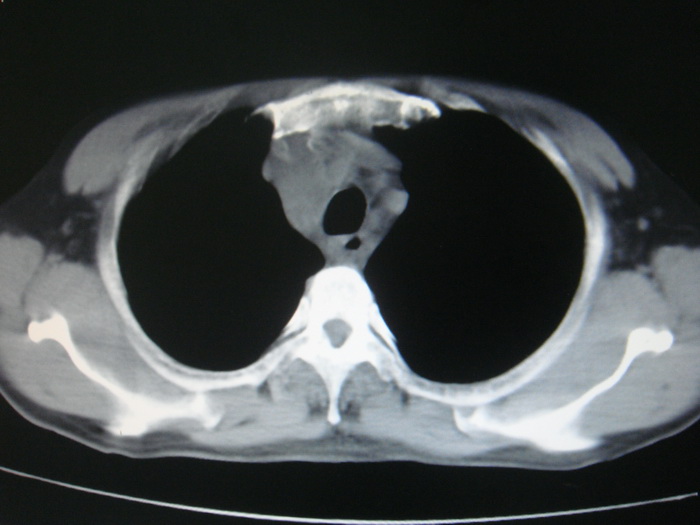

标题: CT28366:男性,45岁,偶尔发现右颈部肿块行胸部CT扫描。 [打印本页]

男性,45岁,偶尔发现右颈部肿块行胸部ct扫描。

两肺多发结节灶及纵膈淋巴结肿大考虑为转移

两肺多发性转移瘤,纵隔淋巴结转移。

两肺多发性转移瘤,纵隔淋巴结转移。食道中上段管壁似乎增厚,作相关检查。

两肺多发性转移瘤,前上纵隔淋巴结转移。